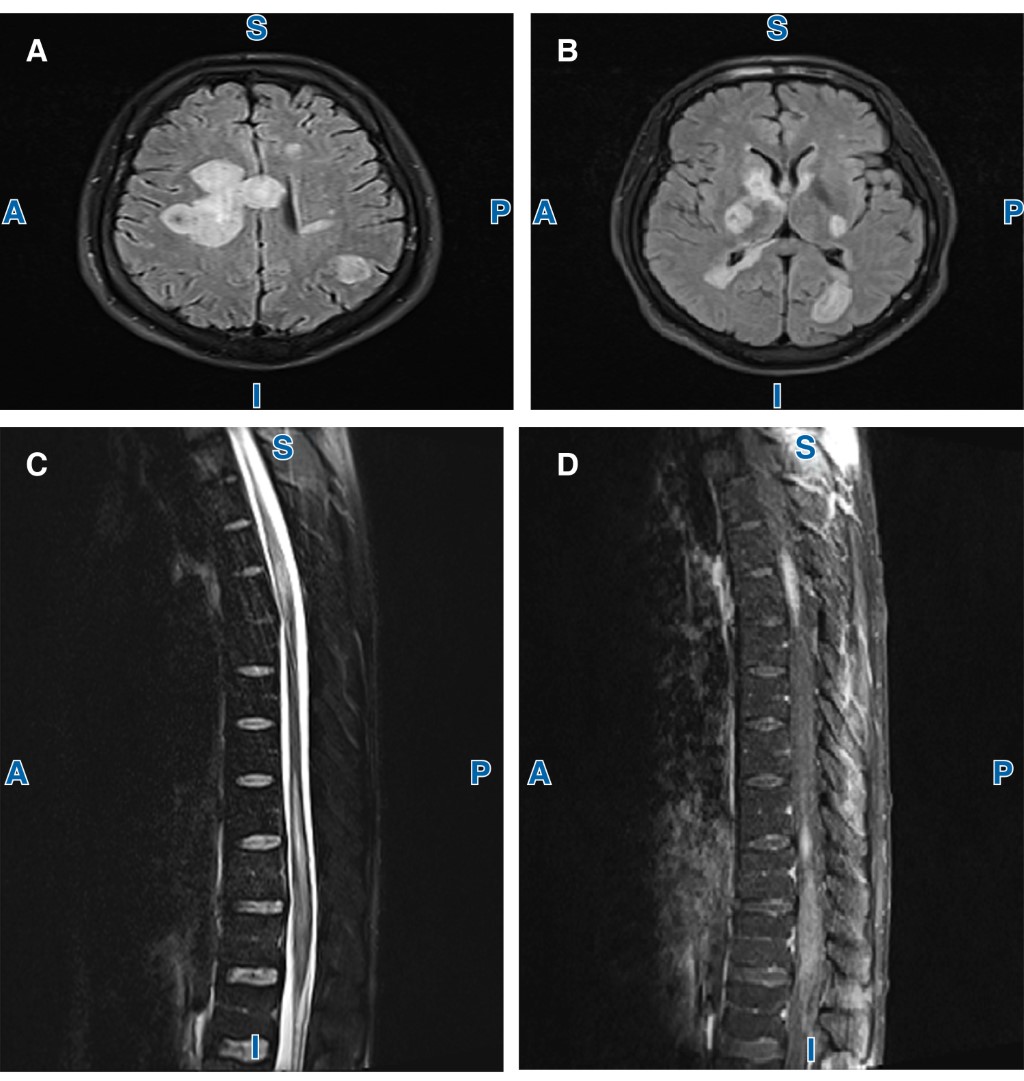

La imagen de resonancia magnética (IRM) cerebral mostró lesiones hiperintensas en T2 en la sustancia blanca, de localización supratentoriales e infratentoriales de predominio en región periventricular, centros semiovales, occipital izquierdo y en cápsula interna izquierda con reforzamiento anular al medio de contraste (Figura 1).